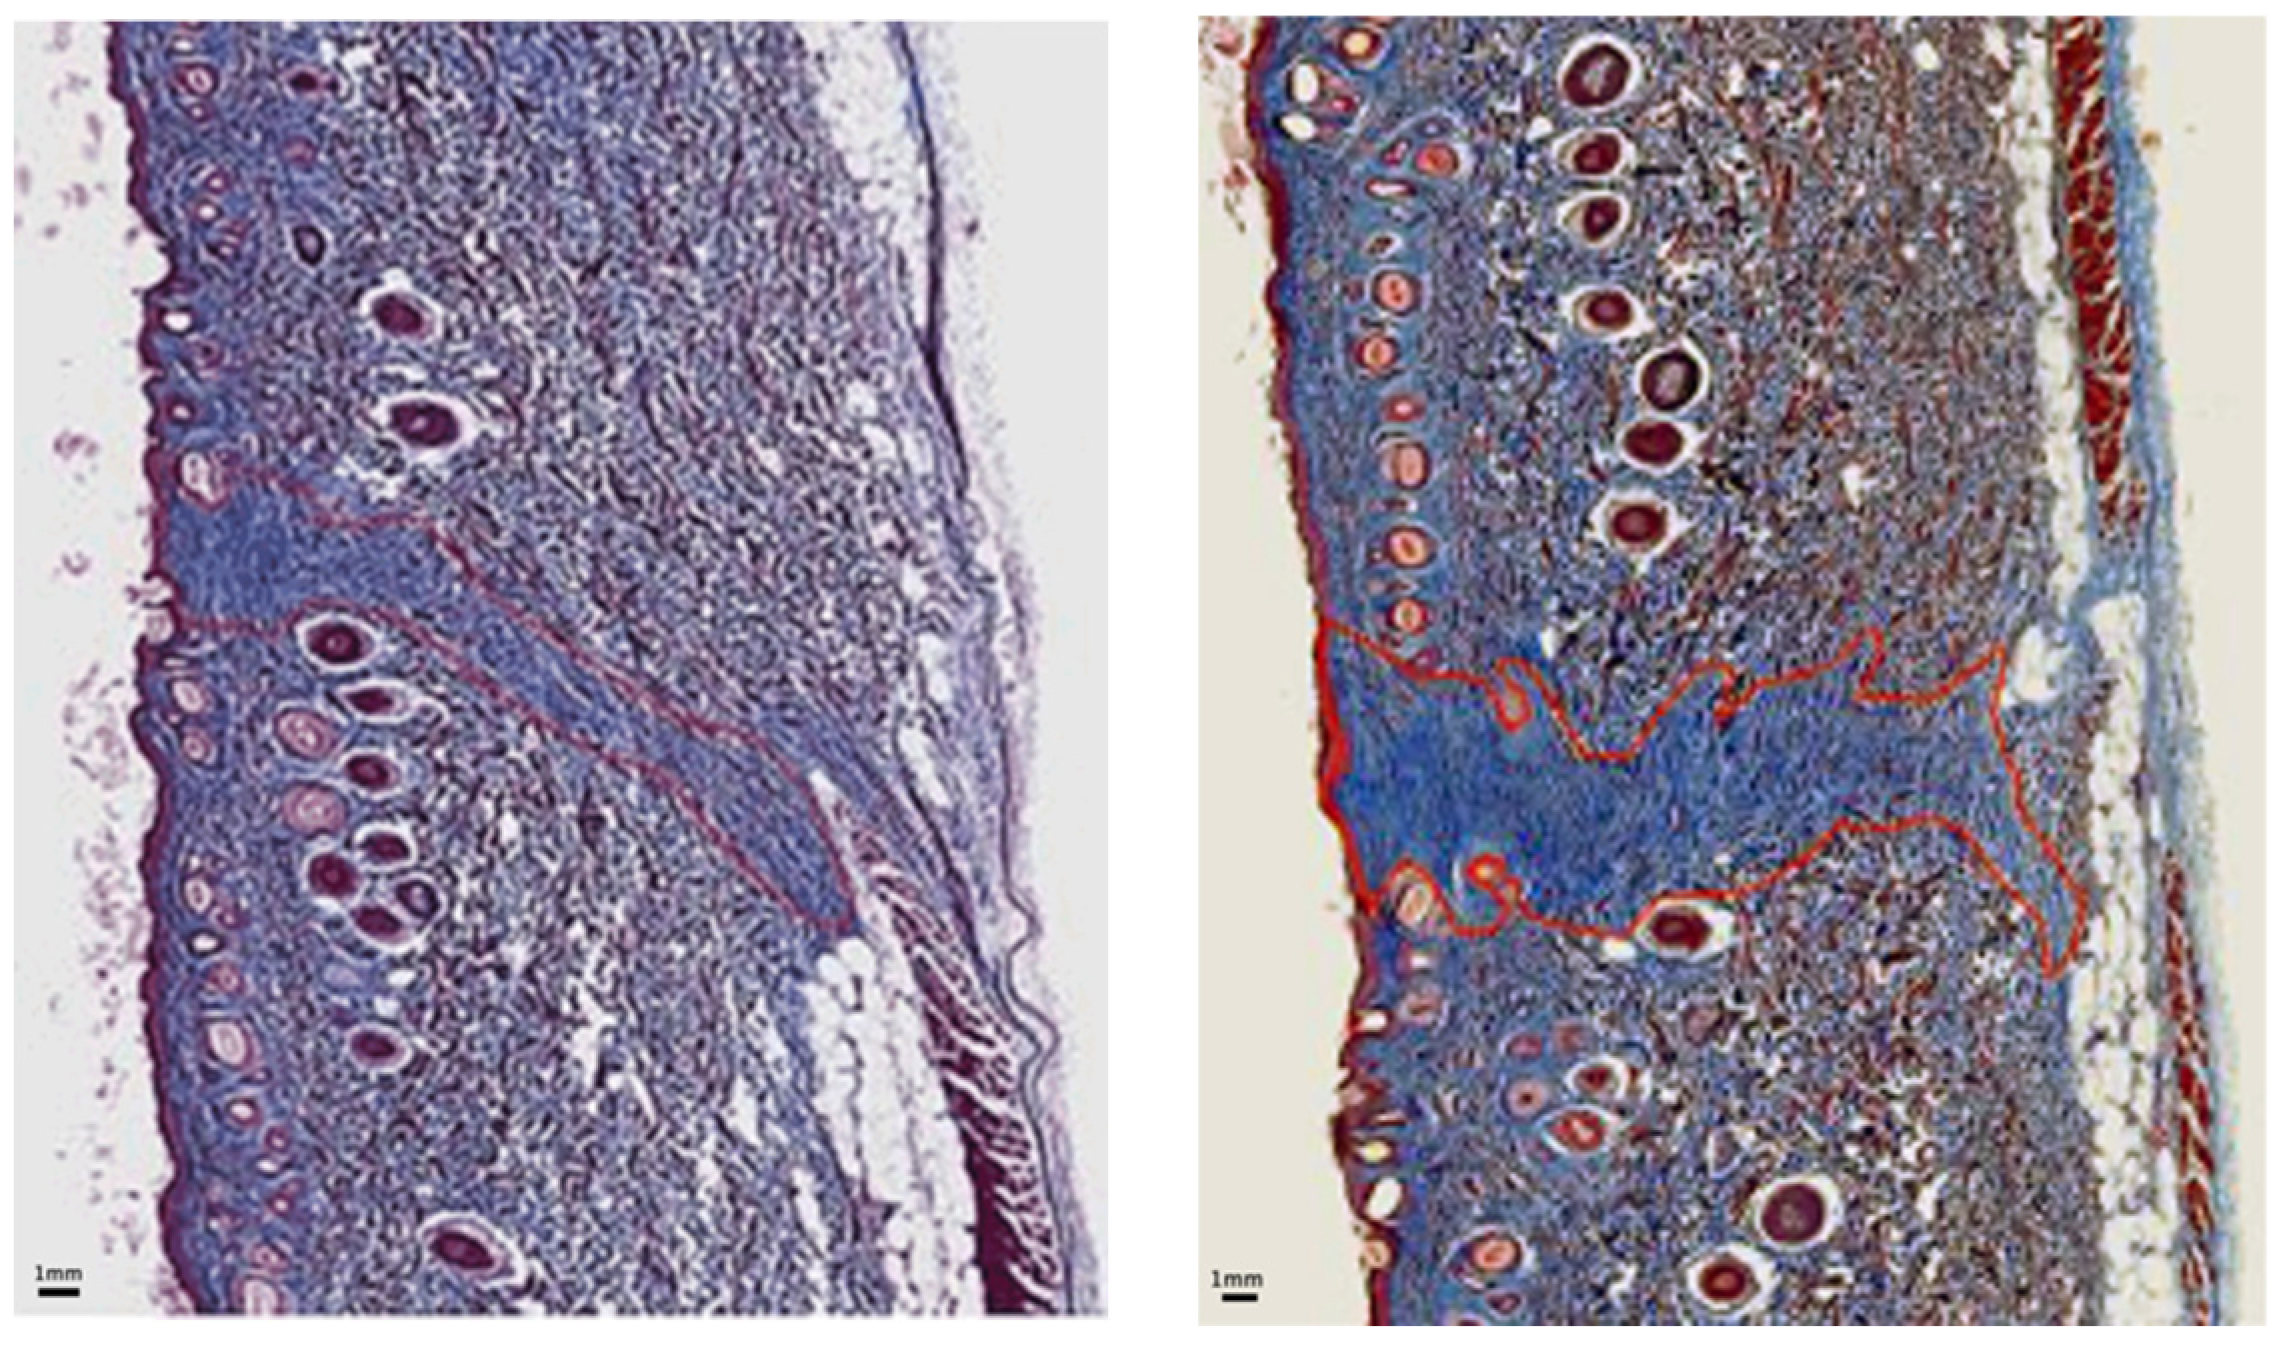

The amount of granulation tissue surrounding each incision was calculated from trichrome-stained sample cross-sections. Granulation deposition was not detectable 24 h after incision but was noticeable at the beginning of day 3.

Figure 7 presents the average values of the C = ratio measuring the decrease in the granulation tissue deposition area in the skin incisions made with the experimental blade CEB relative to the area of skin incisions made with standard blades CSB. The amount of granulation tissue was reduced more in the wounds made with nanometric-scale-polished surgical blades. We observed that C at all time points, which means that notably less granulation tissue occurred in skin incisions made by EBs in comparison with SBs. Generally, the reduction in the granulation tissue deposition area in skin incisions made with the EB ranged between 30% and 50% during the proliferation phase and reached approximately 90% 6 months post-incision, with the magnitude of the standard error of the mean being approximately 25% of the mean on day 7 and about 45% of the mean on day 16 and 6 months post-operation.

Figure 7.

Scar area decrease: Average values and standard errors of C describing the relative decrease in granulation tissue surrounding skin incisions made with EB relative to SB; results derived from cross-sections of trichrome-stained samples on days 7, 16, and 2 months post-surgery.

Figure 8 and Figure 9 are representative images of wound histology at 16 days and 2 months post-surgery, respectively. The difference in the amount of scar produced by the EB versus the SB is apparent. In addition, the scar area width is narrower along the incision made with the EB in comparison with that corresponding to the SB.